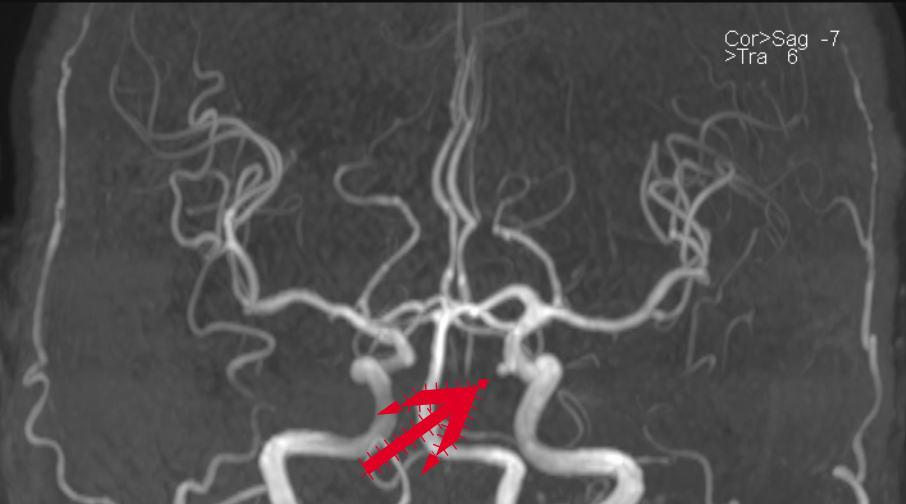

该患者是一名中年男性,因周围性面神经麻痹在我神经内科一区住院,住院期间完善头颅MRA提示可疑左侧颈内动脉眼动脉段动脉瘤(图1),脑血管造影及3D图像重建明确了左侧颈内动脉眼动脉段动脉瘤形态,位置及大小(图2)。

图1